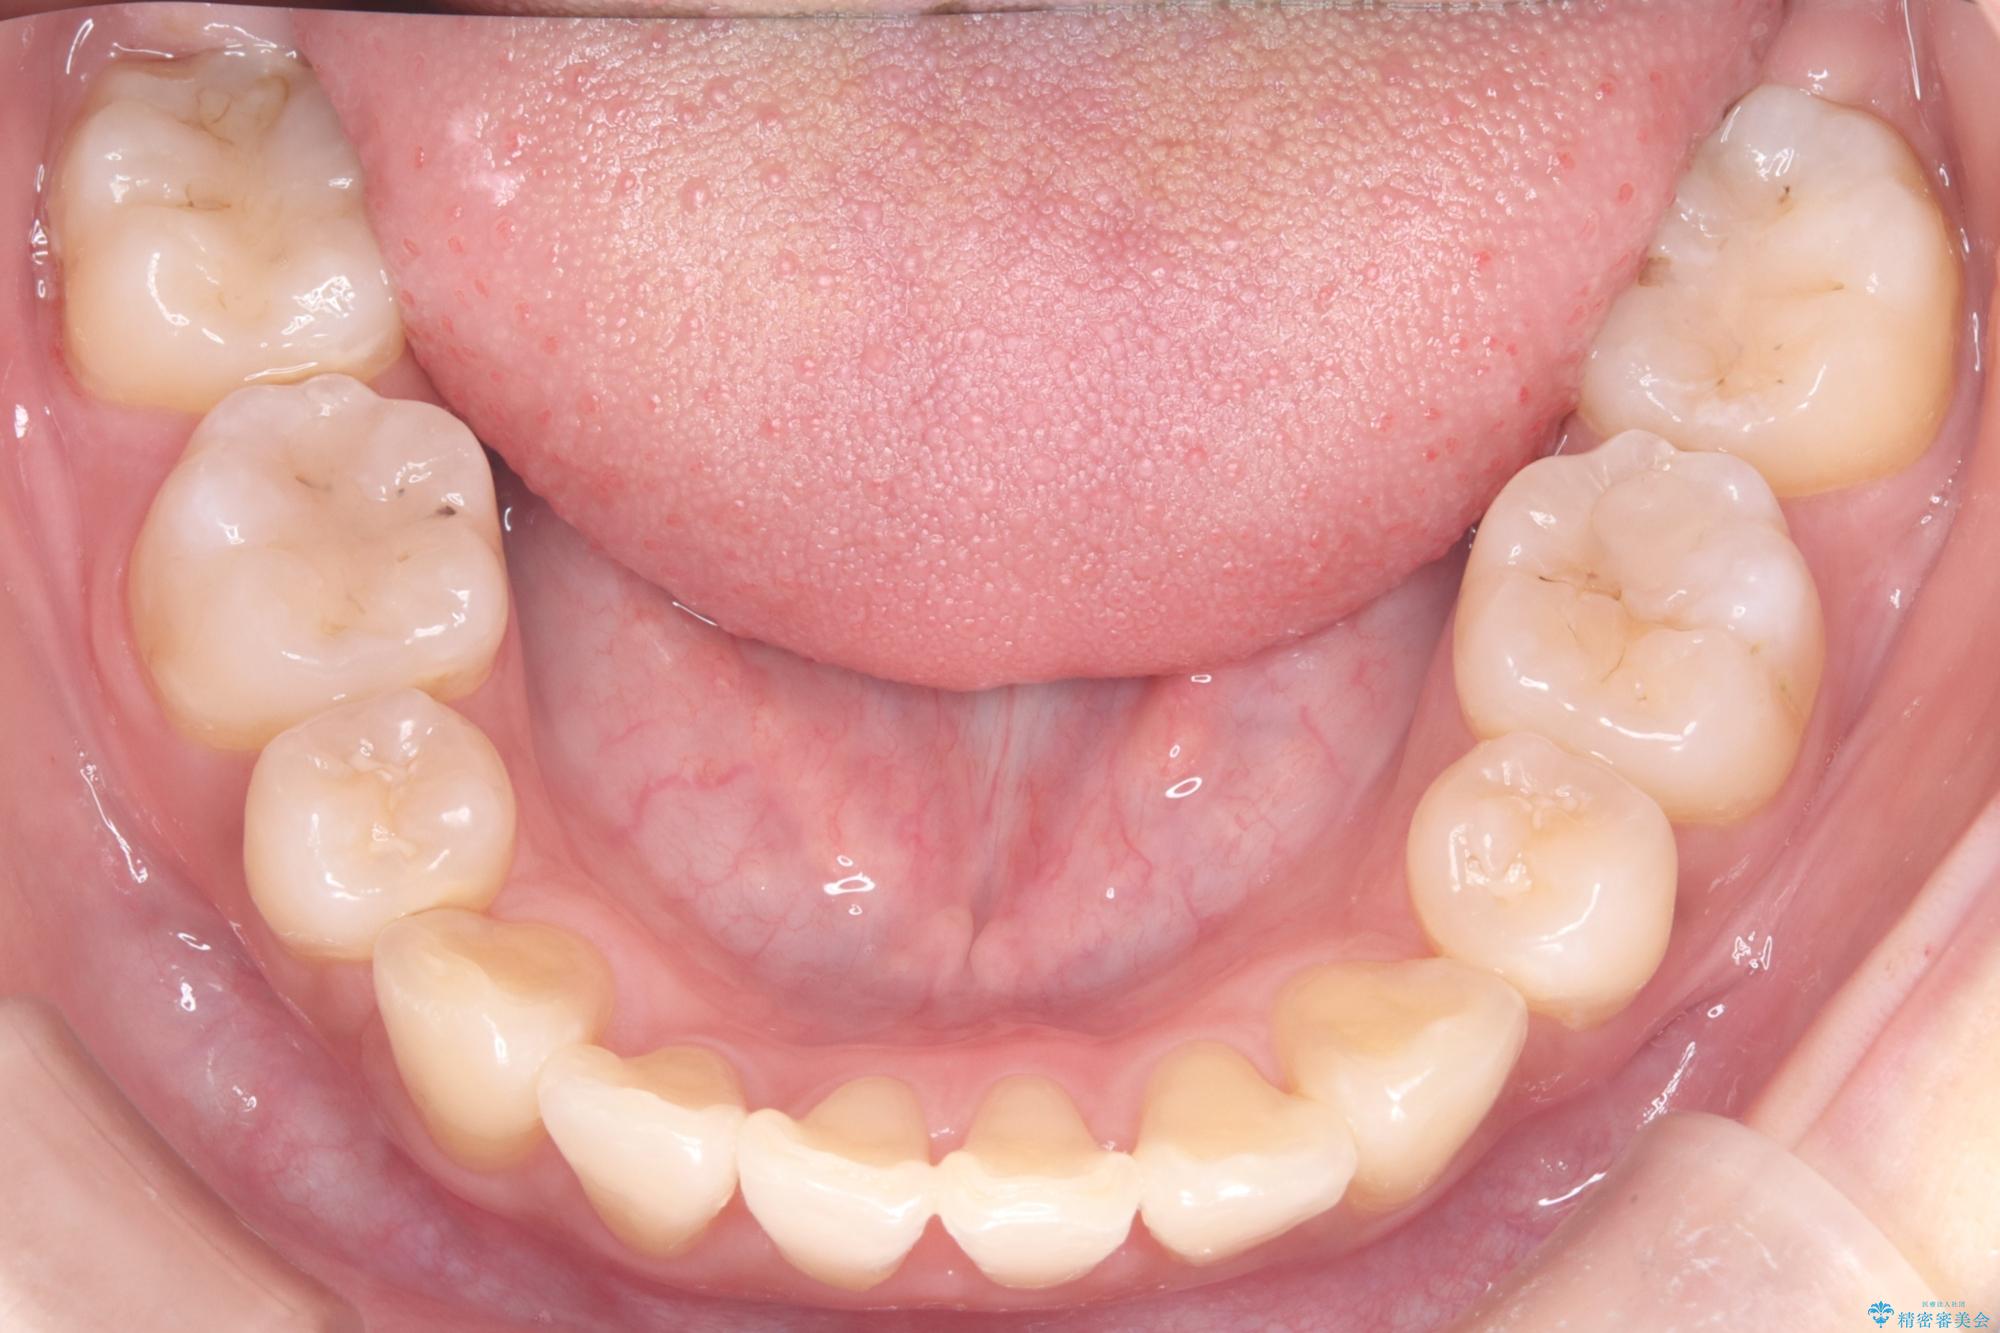

八重歯: 突出していた八重歯を歯列内に誘導し、デコボコを解消しました。

正中のズレ: 歯を左右対称に移動させることで、上下の歯の中心線を正確に合わせ、顔全体のバランスも改善しました。

治療の結果、長年気にされていた八重歯と正中のズレが解消し、機能的にも整った理想的な歯並びを獲得。目立たない装置で治療を完遂し、自信を持って笑える美しい笑顔を手に入れていただけました。